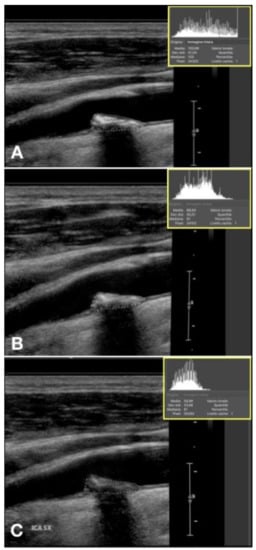

Figure 9.

Plaque showing echogenicity decrease in 12 months treatment with vitamin K2. (A) start, GSM 103, (B) 6 months, GSM 91, (C) 12 months, GSM 61.